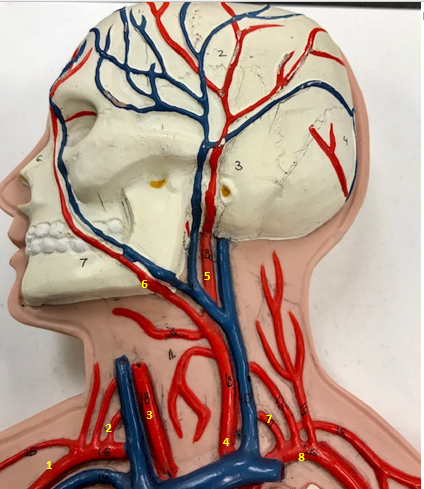

Right subclavian artery

Name #1

Supplies blood to right arm and shoulder

Function of right subclavian artery (1)

Right vertebral artery

Name #2

Supplies blood to brain and spinal cord

Function of right vertebral artery (2)

Right common carotid artery

Name #3

Supplies blood to right neck and head

Function of right common carotid artery (3)

Left common carotid artery

Name #4

Supplies blood to left neck and head

Function of left common carotid artery (4)

Left external carotid artery

Name #5

Supplies blood to face neck and skull

Function left external carotid artery (5)

Left facial artery

Name #6

Supplies blood to face and neck

Function of left facial artery (6)

Left vertebral artery

Name #7

Supplies blood to brain and spinal cord

Function of left vertebral artery (7)

Left subclavian artery

Name #8

Supplies blood to left arm and shoulder

Function of left subclavian artery (8)